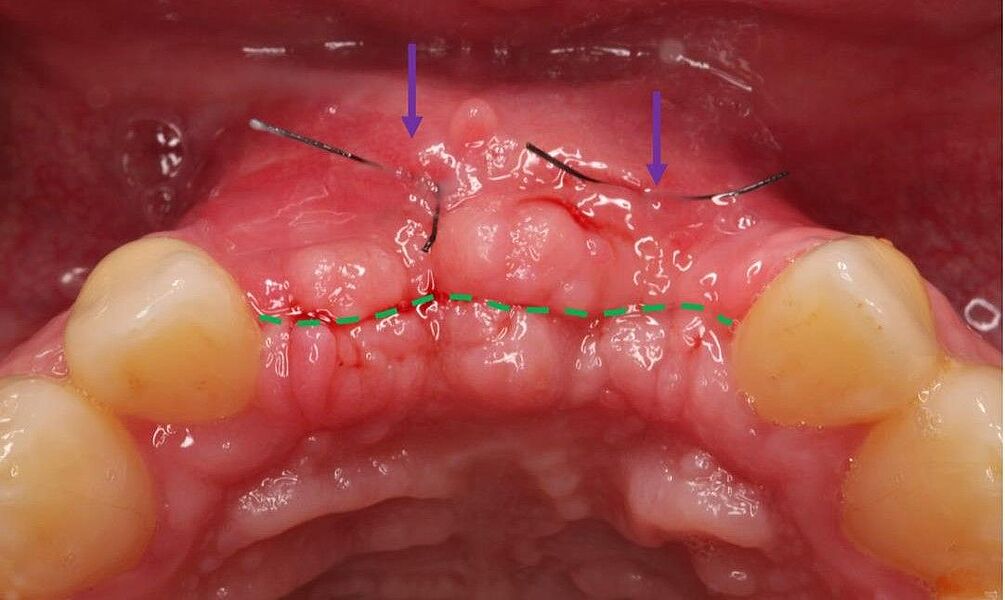

Eine neue Kasuistik zur Rehabilitation bei einer sehr komplexen Ausgangslage in der ästhetischen Zone ist in der Zeitschrift Implantologie des Quintessenz-Verlages erschienen. Als einzige deutschsprachige Zeitschrift aus dem zahnmedizinischen Bereich verfügt die Implantologie über einen kleinen Impact Factor. Konkret stellen die beteiligten Autoren in ihrem 13 Seiten umfassenden Case Report ein synoptisches Behandlungskonzept zur Rekonstruktion zu Verlust gegangener Hart- und Weichgewebe vor. Sie zeigen bei einer 31-jährigen Patientin die Umsetzung einer restaurativen Rehabilitation im anterioren Oberkiefer nach Zahnverlust und beidseitigen Nichtanlagen der seitlichen Schneidezähne.

Zeitschrift: Implantologie

Ausgabe: 02/2022, Seiten 203 – 215

Autoren: Dr. Eleftherios Grizas, Dr. Anna Gutbrodt, Dr. Julian Arnold, alle Dorow Clinic Lörrach, Dr. Dr. Hans Ulrich Brauer, M.A., M.Sc., Akademie für Zahnärztliche Fortbildung Karlsruhe